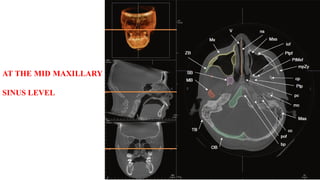

AT THE MID MAXILLARY

SINUS LEVEL

AT THE MIDMAXILLARY SINUS LEVEL